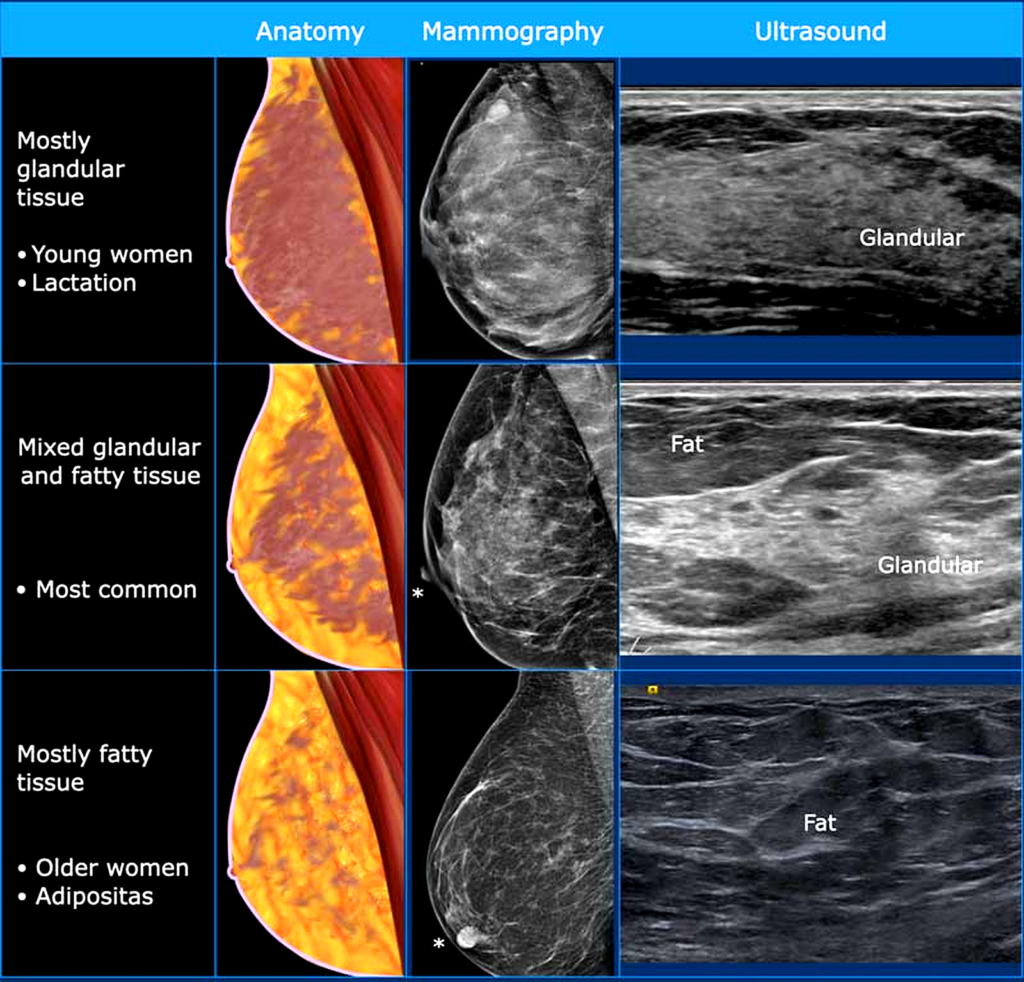

- Ultrasound / Mammography